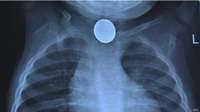

Las pilas pequeñas, en forma de botón, causan al año miles de lesiones, algunas fatales, sobre todo en niños.

Sólo en Estados Unidos hay 3.000 ingestiones al año de pilas.